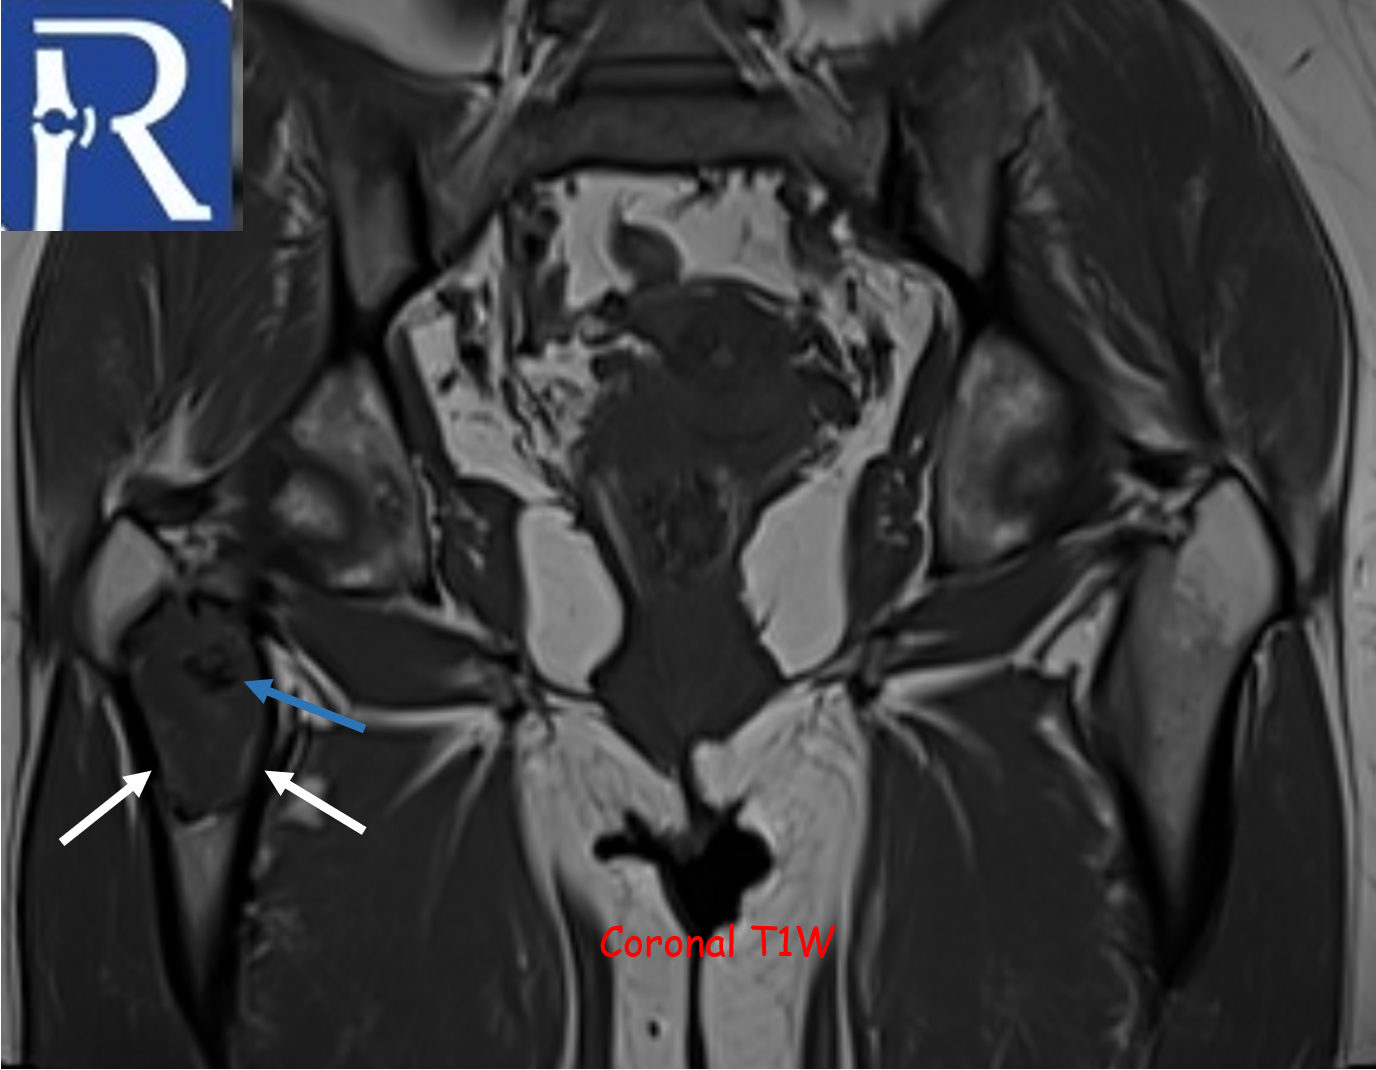

A geographic lytic lesion of Type I A pattern (white arrows) is observed on the right femur intertrochanteric-subtrochanteric area on the pelvic radiograph. The lesion is well-circumscribed and has a narrow transition zone. The internal content contains calcification (indicated by the blue arrow). Periosteal reaction is not visualised. The lesion demonstrates sclerotic areas corresponding to internal calcified foci. The lesion is compatible with liposclerosing myxofibrous tumors. In CT, the lesion matrix structures are more clearly visible, and the cortex appears intact. Calcification areas in the internal structure are more clearly observed. In MRI, the lesion appears as a low signal on the T1-weighted (T1W) sequence and as a high signal on the short tau inversion recovery (STIR) sequence, representing the myxoid content. Additionally, the calcification areas within the lesion exhibit low signals in both sequences.